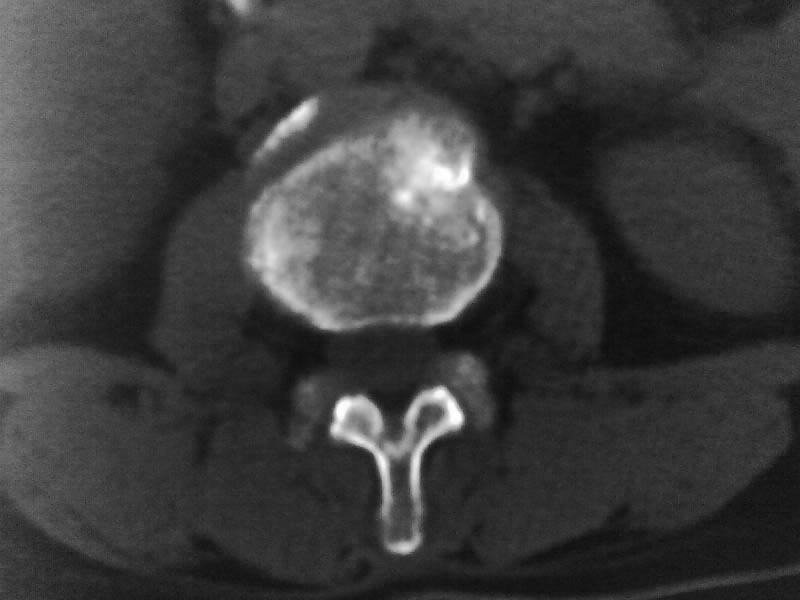

定位相示l2呈楔形改变(ct示陈旧性骨折改变,图像未传),l4.5椎体融合,以下是l4.5ct平扫.请各位看看,

考虑结核(有破坏、硬化及死骨)。

1、三四椎体结核,2、水平骶椎。

2、l3、4椎体结核。

2、l3、4椎体结核。(融合)

就是腰1压缩性骨折,腰3\\4椎体结核(融合),水平骶椎.

腰3、4结核

支持 l1椎体陈旧性压缩性骨折;l3、4椎体结核(融合);水平骶椎。